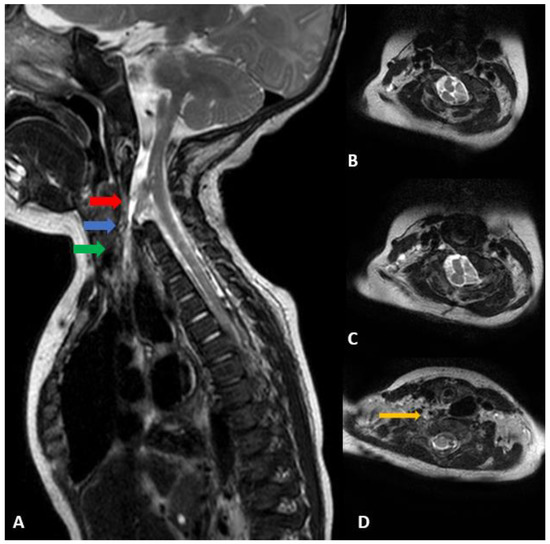

2.3. Diagnostic Assessment